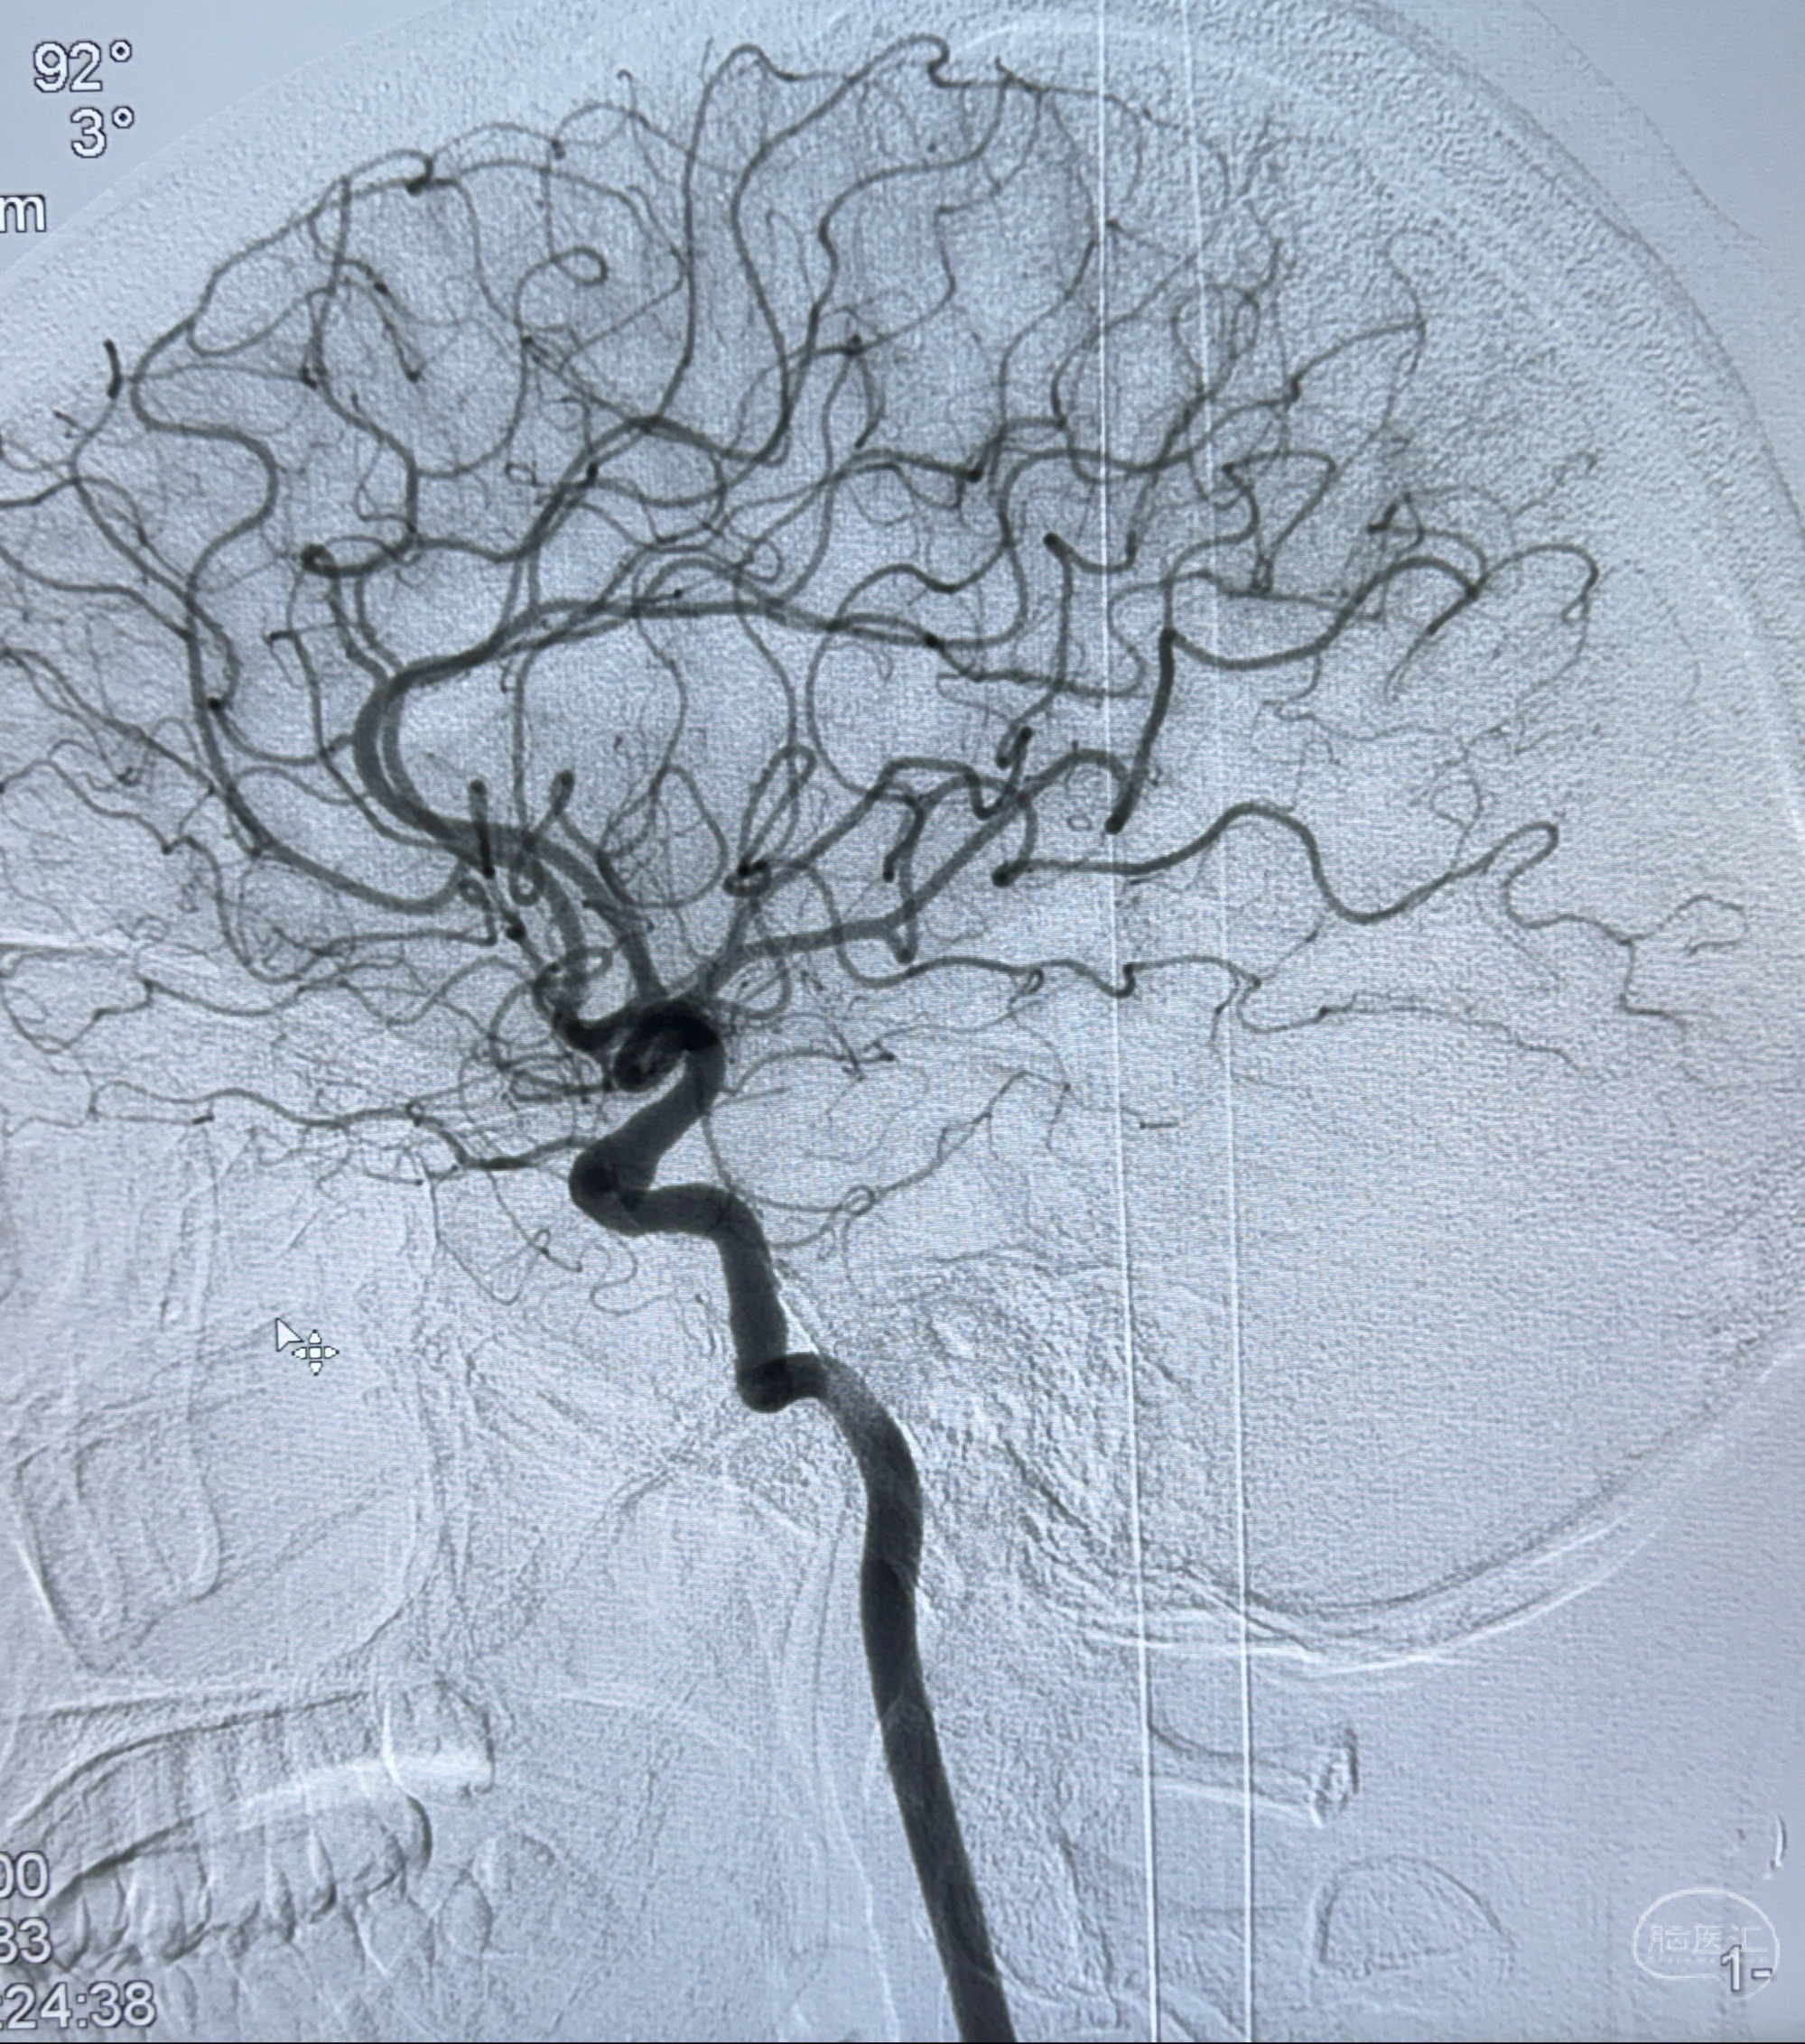

现病史:患者诉近4年来时有头痛发作,服用都梁软胶囊、氟桂利嗪对症治疗一月后症状改善,后头痛较少发作。近3月来患者头痛发作频率明显增加,约一月一次,为右侧偏头痛,胀痛,伴恶心呕吐,呕吐后症状可略减轻;遂于2023-11-01至蓝十字脑科医院就诊,查头颅MRI+DWI+MRA提示:左侧枕叶皮层下小斑片缺血或变性灶,右侧大脑前动脉A1段毛糙,显影淡、纤细,建议完善CTA;并于2023-11-03查头颅CTA提示:左侧颈内动脉C6段微小动脉瘤可能(约2mm),右侧大脑前动脉A1段纤细(对侧优势),左侧大脑中动脉提前分叉。现患者无明显不适,为求进一步诊疗颅内血管病变至我科就诊,收治入院。

2023-11-03 蓝十字脑科医院 头颅CTA:左侧颈内动脉C6段微小动脉瘤可能(约2mm),右侧大脑前动脉A1段纤细(对侧优势),左侧大脑中动脉提前分叉。

1.左侧颈内动脉瘤